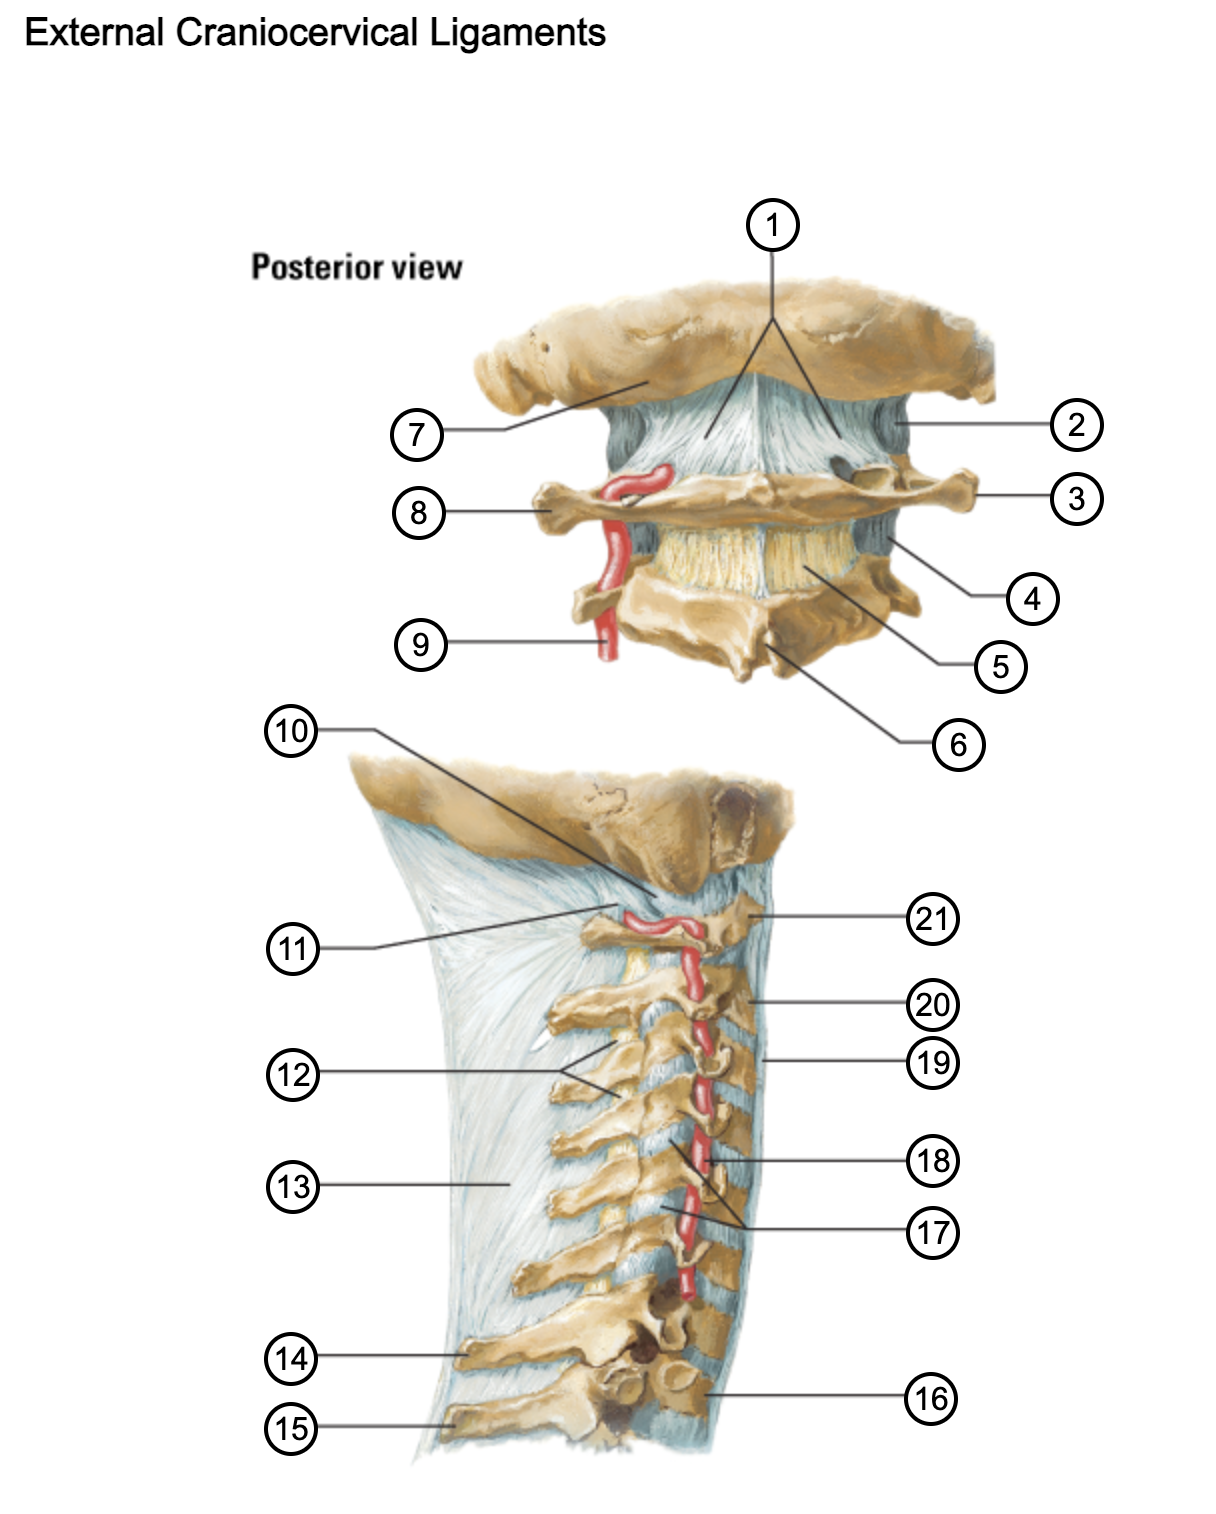

1

posterior antlantooccipital membrane

2

capsule of atlantooccipital joint

3

transverse process of atlas (C1)

4

capsule of lateral atlantoaxial joint

5

ligamenta flava

6

spinous process

7

occipital bone

8

transverse process of atlas (C1)

9

vertebral artery

10

capsule of atlantooccipital membrane

11

posterior atlantooccipital membrane

12

ligamenta flava

13

nuchal ligament

14

spinous process of C7 vertebra

15

spinous process of T1 vertebra

16

T1 vertebra

17

zygapophysical joints (C4-5 and C5-6)

18

vertebral artery

19

anterior longitudinal ligament

20

body of axis

21

Atlas (C1)